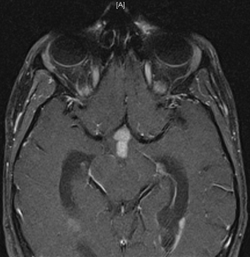

Difficile d'en croire ses yeux

Dr Cécile Faure-Conter Institut d\'Hémato-Oncologie Pédiatrique - Lyon

Antécédent : né en 1987. Aîné de 2, caucasien, pas d’antécédent personnel ou familial, scolarisé en 4ème sans difficulté.

Symptomatologie initiale :

Novembre 1999 (12 ans) : migraines → scanner normal

Mars 2000 : baisse de l’acuité visuelle œil gauche, FO normal : diagnostic de NORB → traitement par cortisone, amélioration partielle.

Juillet 2000 : céphalée et déficit visuel persistant → IRM